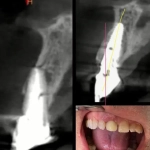

Cas clinique du Dr. Demes avec les implants Co-Axis®

Le patient de 80 ans présente une instabilité fonctionnelle et esthétique liée à une prothèse amovible maxillaire mal tolérée, associée à une occlusion bout-à-bout responsable d’une usure avancée de la prothèse implanto-portée mandibulaire, malgré des volumes osseux maxillaires favorables en zones I, II et III.

Avec la collaboration du Dr. Estelle Demes